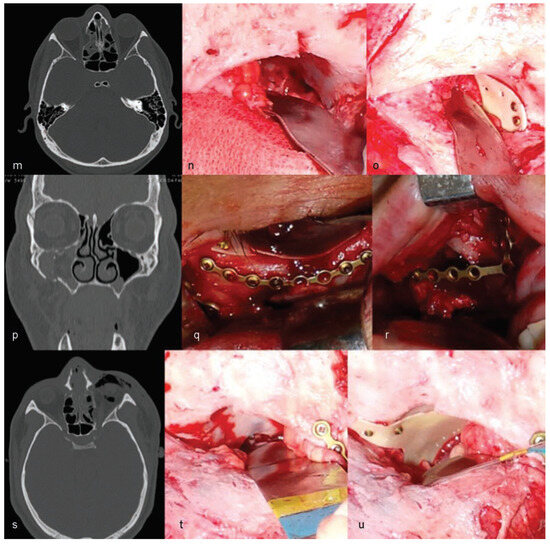

The authors are experienced with the use of castor oil polymer prostheses in several cases of trauma and surgery for camouflage deformities (Figure 1 and Figure 2).

Figure 2. Cases of patients treated with the use of castor oil polymer prosthesis II: (mo,su) Orbital medial wall fractures. (pr) Orbital floor fractures.